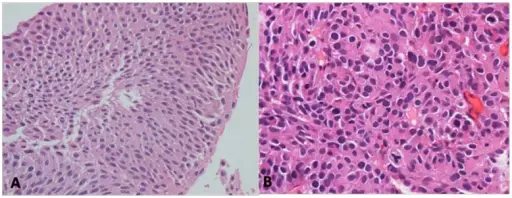

When examined under a microscope, the most common variant of renal cell carcinoma shows clear cytoplasm or a clear cell type.

Loss of the tumor suppressor gene VHL causes an increase in the growth-promoting hormone IGF-1 and the transcription factor HIF, which in turn causes an increase in the growth hormones VEGF and PDGF.

Renal Cell Carcinoma (RCC)

Renal cell carcinoma (RCC) is a malignant cancer cells are located in the lining of kidney tubules, which are incredibly tiny tubes. This condition is known as renal cell carcinoma.